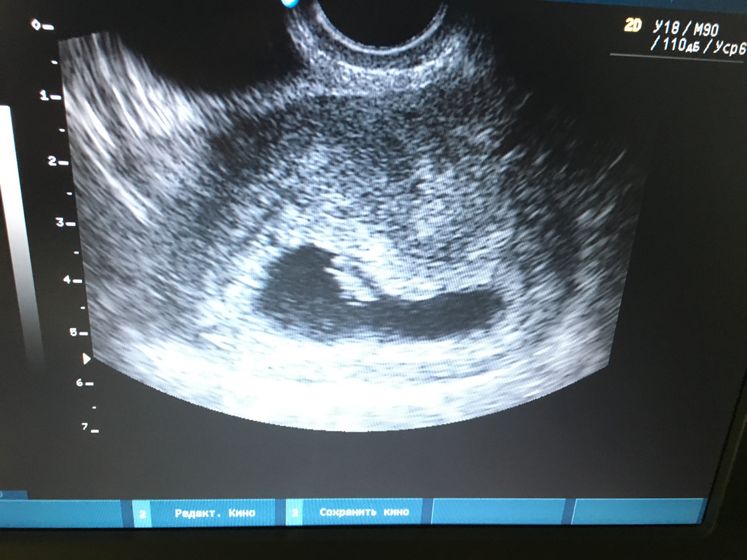

Девочки всем привет) была сегодня на УЗИ срок 6,6 недель. Врач ставит однояйцевые близнецы под вопросом, сказал на скрининге все скажут точно. У кого так было на таком сроке и в итоге оказались близняшки?)

Я вообще не спец, но как человек я вижу одно плодное яйцо, будто под тонусом, и одного малыша на данном фото. Может быть это два яйца, но в правой части его я здесь ничего не вижу, может он "младший" и пока не визуализируется.

При однояйцевых близнецах плодное яйцо одно и должно быть)

Это я понимаю, но в правой его части, где скорее всего поселится второй малыш, на этом снимке ничего не вижу. На своём снимке я и жм не видела, но видел врач и описал в результате обследования. Так что им виднее, кто там))

Видимо на таком сроке не особо видно, поэтому и под вопросом?